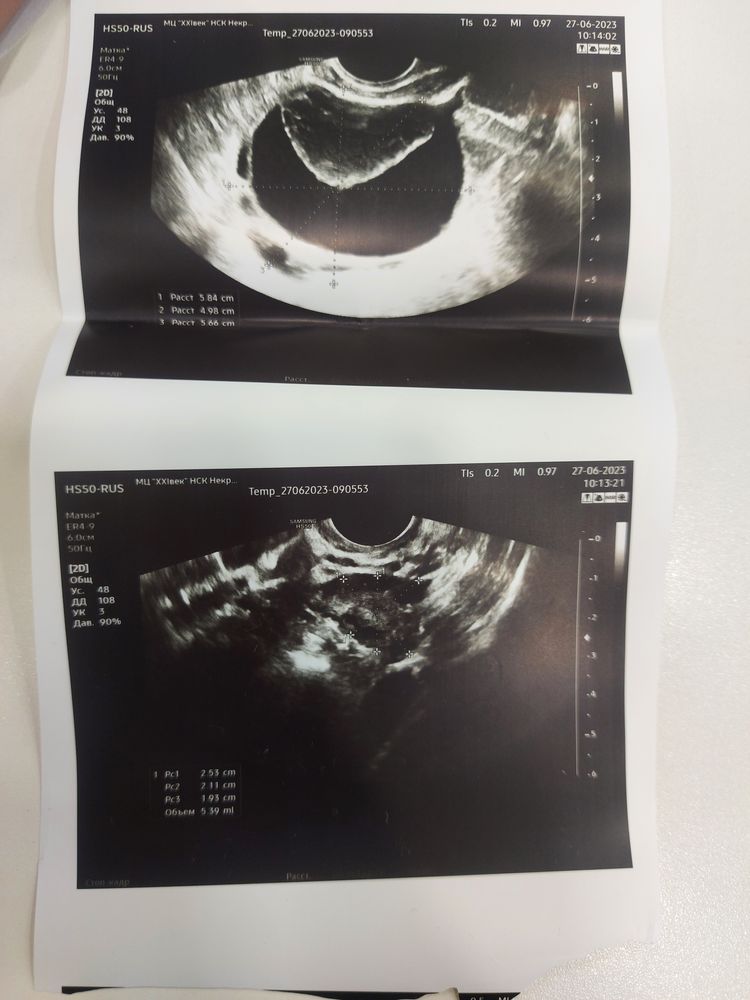

26 июня у меня пошли месячные на 26 день цикла( хотя обычно он 35 дней), в это же время на узи обнаружили кисту в яичнике 5 см 😬 мультифолликулярные яичники, андрогения - как сказала врач